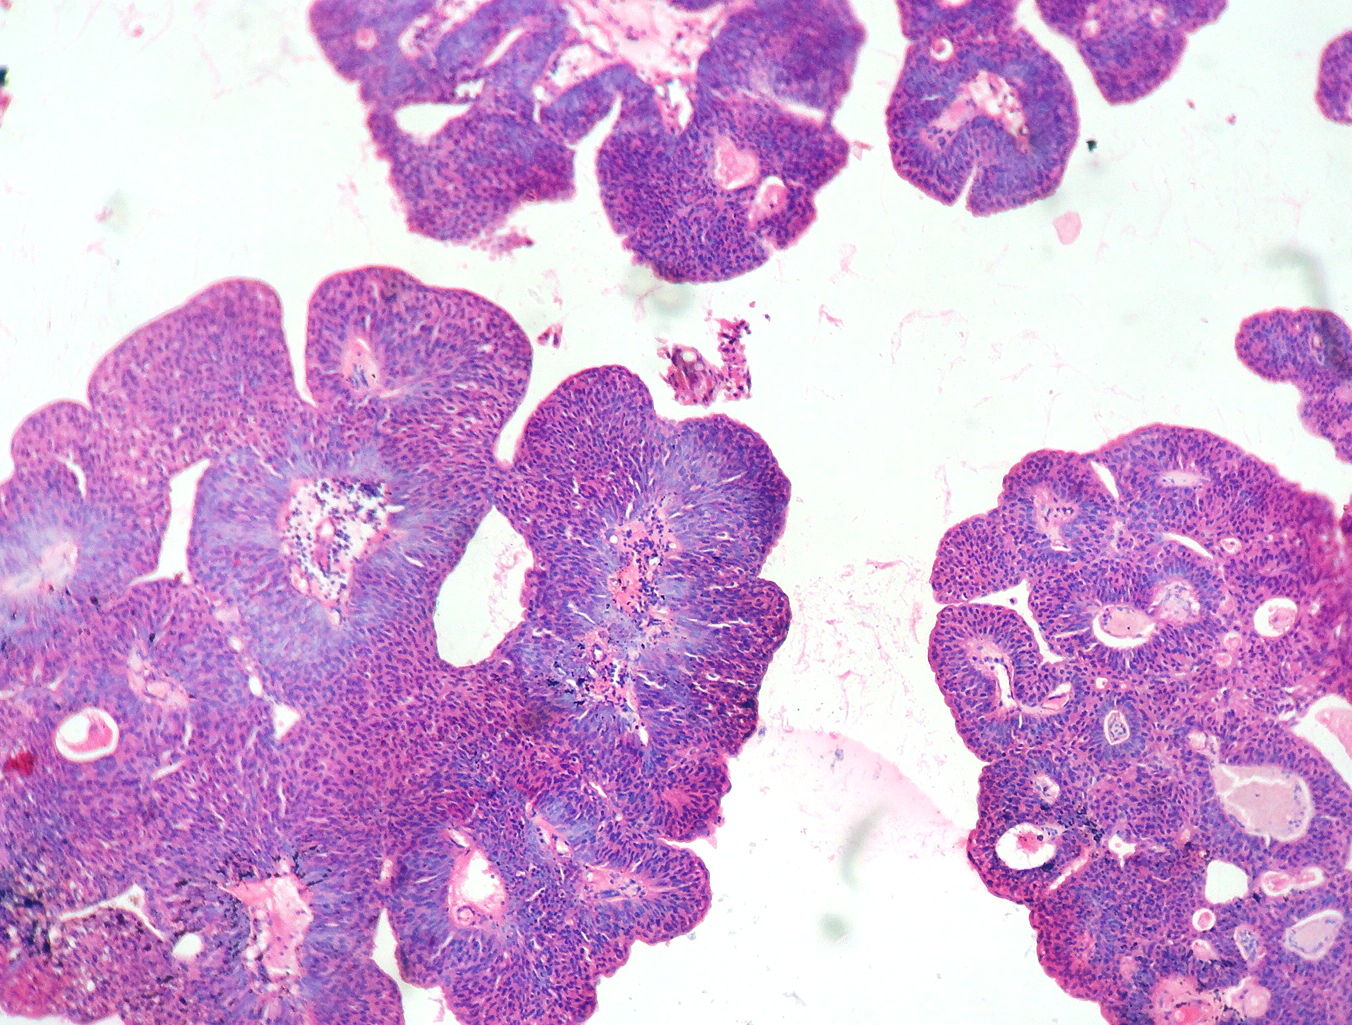

In our study, we made an attempt to evaluate the pattern of tumor growth, its degree of differentiation, progression and associated mucosal changes. In 15 cases of urothelial papilloma, it is characterized by discrete papillary growth with a central fibrovasular core lined by urothelium of normal thickness and cytology (Figure 1). In five cases of Papillary urothelial neoplasm of low grade malignant potential (PUNLMP), histopathologically the tumor is characterized by delicate, orderly, tenuous papillary structures with orderly arrangement of cells within the papillae with minimal architectural abnormalities and nuclear atypia usually limited to basal layer irrespective of cell thickness (Figure 2). The major distinction from papilloma is that in PUNLMP the urothelium is much thicker and nuclei are significantly enlarged. In 21 cases of low grade urothelial carcinoma, histologically it is characterized with papillary axes which are more compact, crowded, fused at the base and lined by unordered cells showing both architectural and cytological abnormalities with frequent mitosis (Figure 3). In 51 cases of high grade urothelial carcinoma showed fused papillary axes over the large areas resulting in sheets and solid areas. The cells have enlarged, hyperchromatic, pleomorphic nucleus in full thickness of the epithelium with increased atypical mitosis (Figure 4). As per TNM staging used in our study we observed majority of the bladder tumours were invasive accounting for 78.25% (Figure 5 & 6) as compared to non-invasive bladder tumours constituting 21.73% of the cases as shown in table 3.